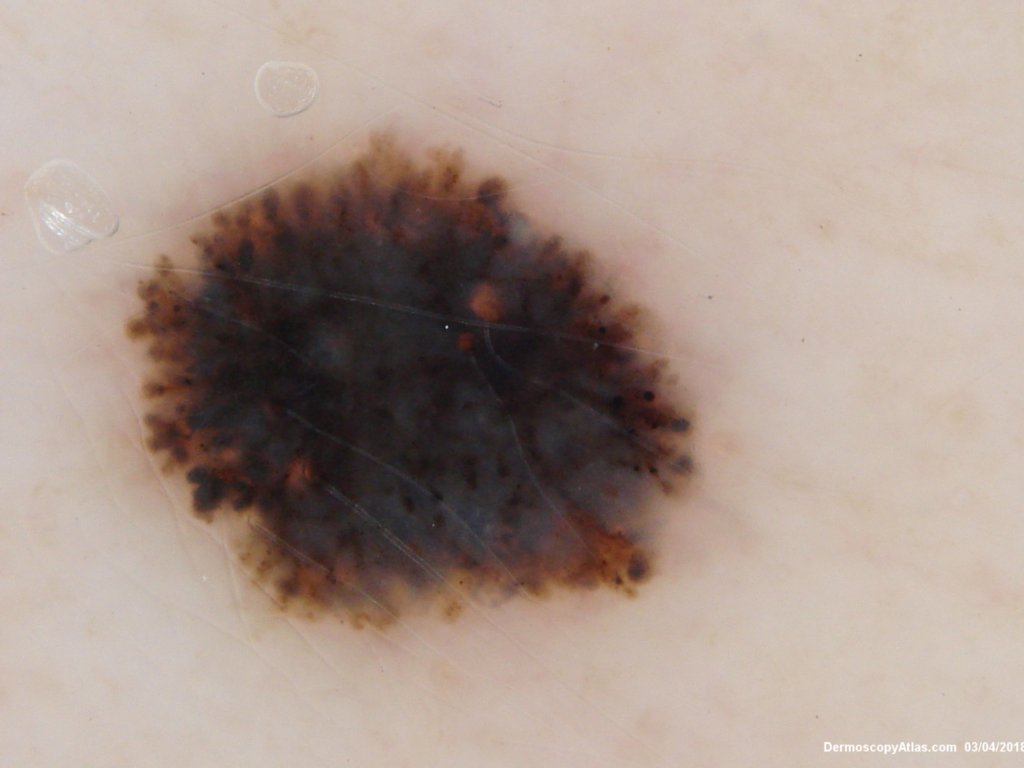

Diagnosis: Reed nevus

Description: Peripheral pseudopods

Sudden onset of a new pigmented lesion on the shoulder. Dermatoscopy shows an actively proliferating lesion with peripheral pseudopods that involve most of the circumference. Clinically this was either a Reed nevus or a Spitzoid melanoma. The histology favours a Reed nevus.